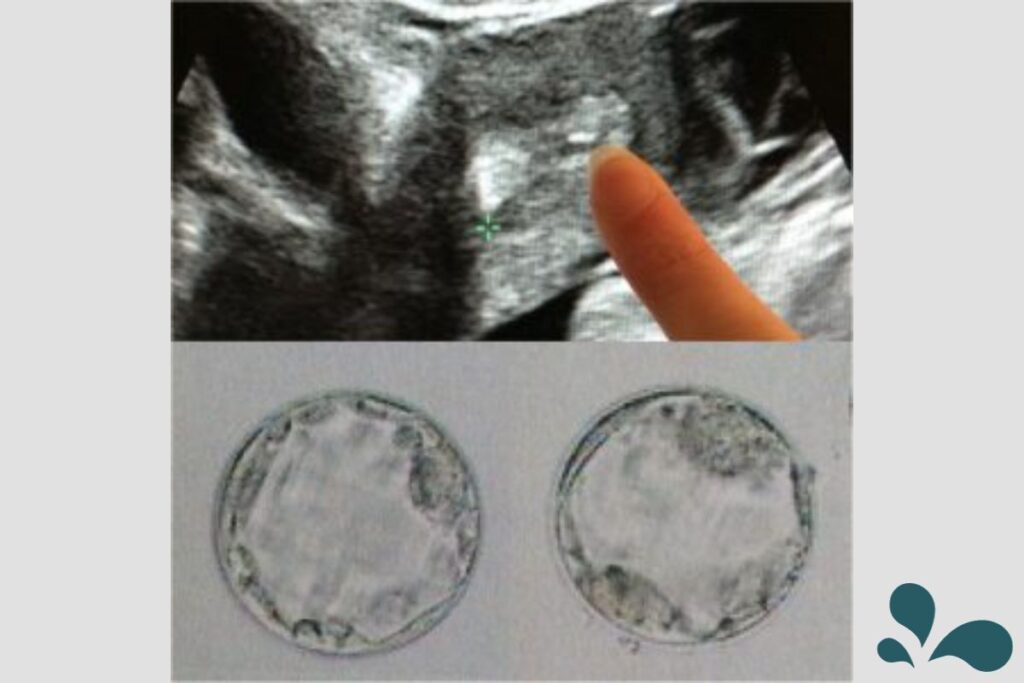

Of the original 42 eggs, 28 were mature. From the 28 mature eggs, 17 fertilized and started growing. They continued to watch them grow and gave me updates. Five days after egg retrieval, I went in for the fresh embryo transfer. There were two embryos that were ready and five embryos that they wanted to monitor for maturity. We had them implant the two embryos that were ready. We decided to implant two because Dr. Foulk, our RE, had mentioned that if we were to put in one embryo, we had a 50% of getting pregnant; by putting in two we had a 75% chance of getting pregnant, with an added 30% chance that we would have twins.

Several days later, they let me know that 3 of the embryos continued to grow and were frozen.